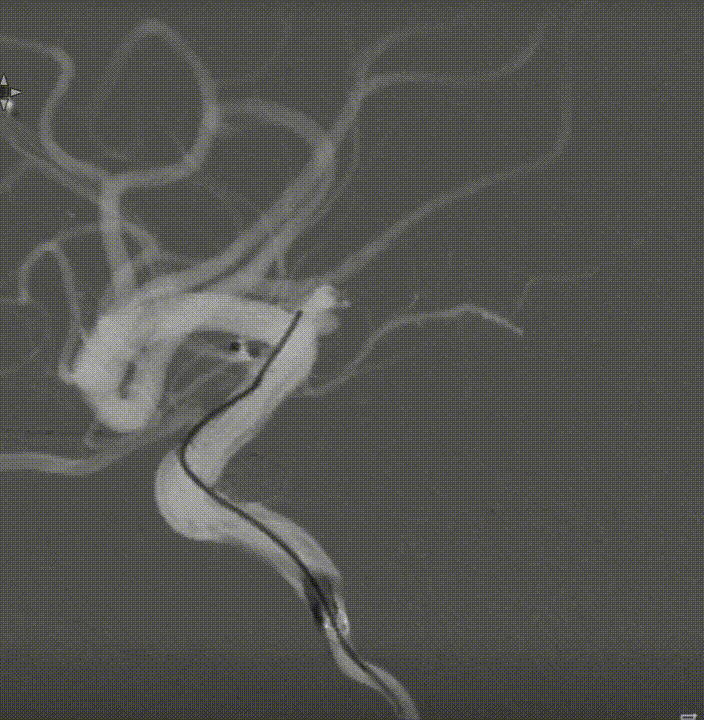

术前外院 DSA 2025-02

箭头所指右侧A1微小动脉瘤

工作位正位造影(图片)

工作位侧位造影(图片)

工作位正位造影(视频)

工作位侧位造影(视频)